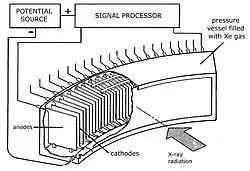

In 1973, David Chesler, a scientist at Massachusetts General Hospital who had previously conducted pioneering work in positron emission tomography (PET), secured funding from the National Institutes of Health (NIH) to develop a CT body scanner utilizing a fan-beam design. His system aimed for a scan time of 5 seconds and featured filtered back-projection reconstruction, a bow-tie filter to reduce beam-hardening artifacts, and quarter-offset alignment to minimize aliasing.[13] Compact detector designs based on Xenon ionization chambers were pivotal to the advancement of third-generation CT scanners.

Pioneering work in detector development was conducted by Douglas P. Boyd[17] at Stanford University, as well as N. R. Whetten and J. M. Houston[18] at GE. In these systems, Xenon gas was compressed within chambers to pressures of 20–30 atmospheres. The chambers contained bias and signal electrodes designed to collect electrons generated by xenon ionization events resulting from X-ray absorption. With cell depths of several centimeters, these detectors achieved detective quantum efficiencies of around 50% for the X-ray spectra used.[13] They also demonstrated superior stability and linearity compared to earlier technologies and the electrodes simultaneously served as anti-scatter grids. Most third-generation CT systems adopted xenon ionization chambers in combination with pulsed X-ray sources, which helped reduce motion blur and offered improved control over radiation dose.[13]

One notable example is the V360-3 CT system introduced by Varian Associates in 1976. It featured a 301-channel ionization chamber, a pulsed X-ray source, and a continuously rotating gantry enabled by early slip-ring technology—allowing for a scan time of just 3 seconds per slice.[13] An alternative detector concept was introduced by Siemens in its 1977 Somatom system, which featured an array of cesium iodide (CsI) scintillators coupled to photodiodes and a rotation time of 4 seconds.[13] Notable innovations included a high-heat-capacity X-ray tube and fast image reconstruction, with filtered backprojection initiated during the scan itself.